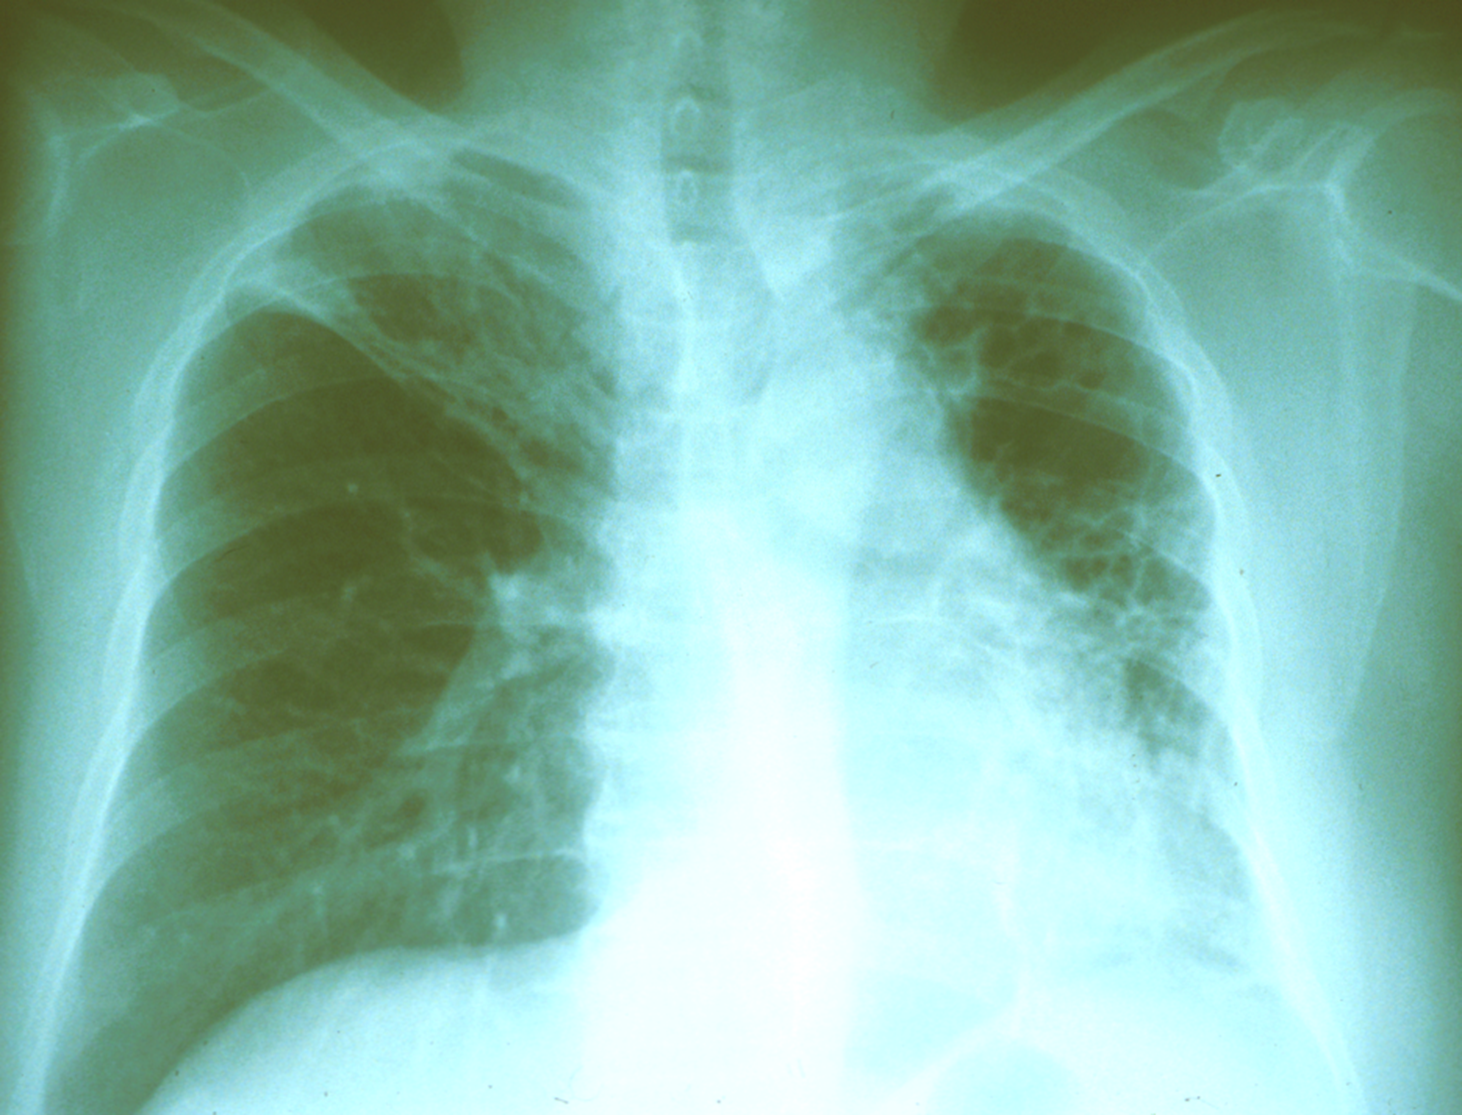

Same 55 y/o Vietnamese who has lived in US for 30 years, but he has the following CXR.

How do you manage him?

TreatÂ

high risk of progressing to TB diseaseÂ

TB Disease Case Rate By CXR Classification In Alaskan Natives

RUL some trouble

Infiltrate

Increase risk of disease progressionÂ

Cavity in LUL

Even if culture negative is concerning

still concerning

Longer prophylaxis _____ progression to tuberculosis disease in patients with fibrotic lesions

decreases